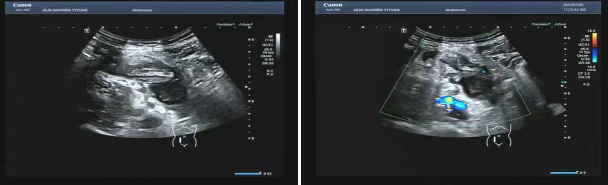

80 歲的張爺爺(化名)因前列腺增生前往國文醫(yī)院就診,泌尿外科為其開具了泌尿系超聲檢查。超聲科醫(yī)生在檢查過程中,憑借敏銳的觀察力,發(fā)現(xiàn)患者右下腹有異?;旌匣芈暟鼔K。醫(yī)生沒有放過這一異常,立即展開進一步探查,結(jié)果顯示包塊內(nèi)疑似有闌尾結(jié)構(gòu),且周圍組織存在粘連,還伴有液性暗區(qū)??紤]到老年患者病情往往較為隱匿,癥狀也不典型,醫(yī)生第一時間與臨床醫(yī)生溝通,建議進行緊急處理。隨后,經(jīng)過臨床醫(yī)生詳細檢查,患者迅速辦理住院并接受手術(shù),術(shù)后病理檢查結(jié)果確診為 “闌尾壞疽伴穿孔合并膿腫形成”。

主治醫(yī)生介紹,老年人患闌尾炎時,癥狀常常不典型,很容易被誤診為腸胃炎或其他疾病。張爺爺僅表現(xiàn)出輕微腹脹的癥狀。倘若不是超聲檢查時意外發(fā)現(xiàn),極有可能延誤治療,進而引發(fā)感染性休克,甚至危及生命。超聲檢查在這類急腹癥的篩查中,發(fā)揮了至關(guān)重要的作用。